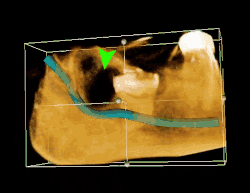

TAC 3D de una muela del juicio impactada adyacente al nervio alveolar inferior antes de la extracción de la muela del juicio. | ||

Si el diente no se puede evaluar únicamente con el examen clínico, el diagnóstico se realiza mediante una radiografía panorámica o una tomografía computarizada de haz cónico. Cuando las muelas del juicio no erupcionadas todavía tienen potencial de erupción, se utilizan varios factores predictivos para determinar la probabilidad de que los dientes se impacten. La relación de espacio entre la longitud de la corona del diente y la cantidad de espacio disponible, el ángulo de los dientes en comparación con los otros dientes son los dos predictores más utilizados, siendo la relación de espacio la más precisa. A pesar de la capacidad de movimiento en la edad adulta temprana, la probabilidad de que el diente se impacte puede predecirse cuando la relación entre el espacio disponible y la longitud de la corona del diente es inferior a 1.:[5] 141

Las complicaciones a largo plazo pueden incluir complicaciones periodontales como la pérdida de hueso en el segundo molar tras la extracción de las muelas del juicio. La pérdida ósea como complicación tras la extracción de las muelas del juicio es poco frecuente en los jóvenes, pero está presente en el 43% de las personas de 25 años o más.[23] La lesión del nervio alveolar inferior que provoca entumecimiento o entumecimiento parcial del labio inferior y la barbilla ha registrado tasas que varían ampliamente del 0,04% al 5%.[23] El estudio más amplio es el de una encuesta de 535 cirujanos orales y maxilofaciales de California, en el que se registró una tasa de 1:2.500.[26]

La coronectomía es un procedimiento en el que se extrae la corona de la muela del juicio impactada, pero las raíces se dejan intencionadamente en su sitio. Está indicada cuando no hay enfermedad de la pulpa dental ni infección alrededor de la corona del diente, y existe un alto riesgo de lesión del nervio alveolar inferior.[32]